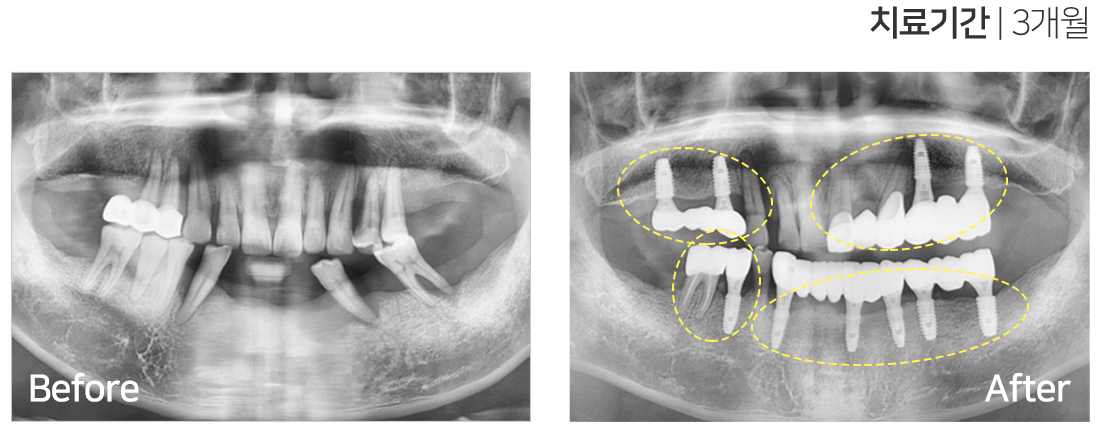

임플란트 시술 사례

IMPLANT TREATMENT CASES

※ 전신질환 및 관리 능력에 따라 임플란트 주위염 등의 부작용이 있을 수 있습니다.